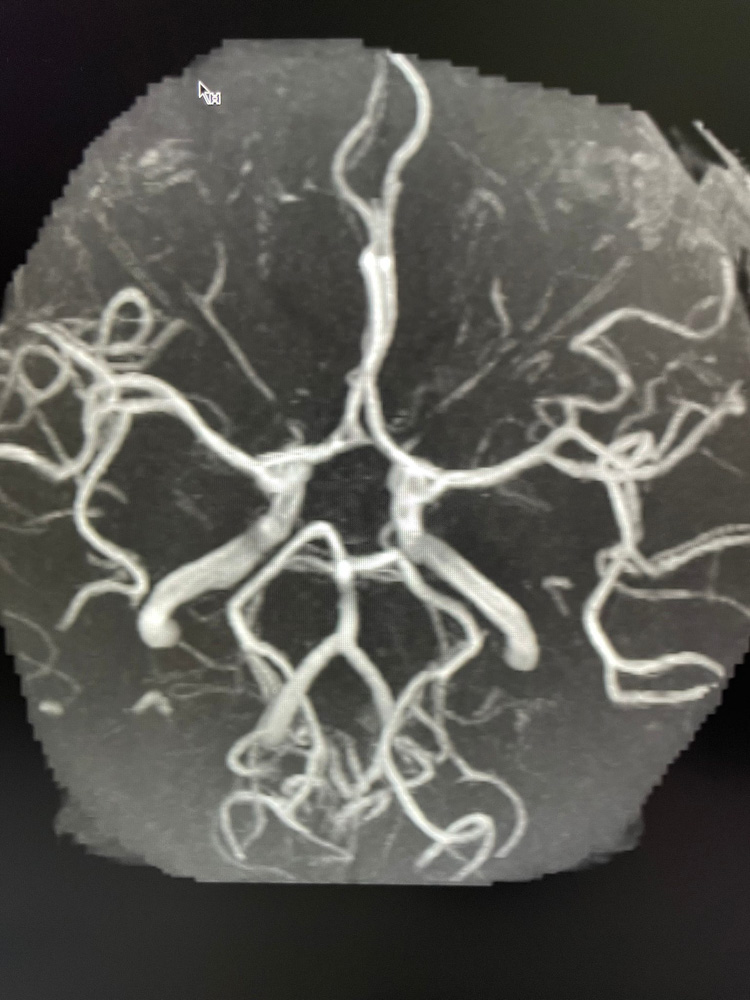

Das Aufgabengebiet der Neuroradiologie umfasst die Diagnostik von Erkrankungen und Veränderungen des Zentralen Nervensystems (ZNS), d.h. von Gehirn und Rückenmark. Das Gehirn ist ein äußerst komplexes Organ des menschlichen Körpers, so dass die Neuroradiologie eine mehrjährige Spezialisierung im Fachgebiet Radiologie erfordert, die vergleichbar mit der Kardiologie im Fachgebiet der Inneren Medizin oder der Gehirnchirurgie im Fachbereich der Chirurgie ist.

Diagnostik und Befundung in der Radiologie sind im Verlauf der letzten Jahre immer komplexer und anspruchsvoller geworden. Mit der spezialisierten Neuroradiologischen Diagnostik bieten wir Ihnen in unserer Praxis eine besondere Expertise in der Auswertung Ihrer Untersuchungen an.

Beispiele für spezielle Neuroradiologische Fragestellungen:

4. Abklärung von Kopfschmerzen, Schwindel, Tinnitus, Hör- und Sehstörungen usw.

5. Ursachenforschung bei Lähmung der Gesichtsmuskeln (Facialisparese), Schmerzzuständen der Gesichtshaut (Trigeminusneuralgie) oder Schädigungen der übrigen Hirnnerven